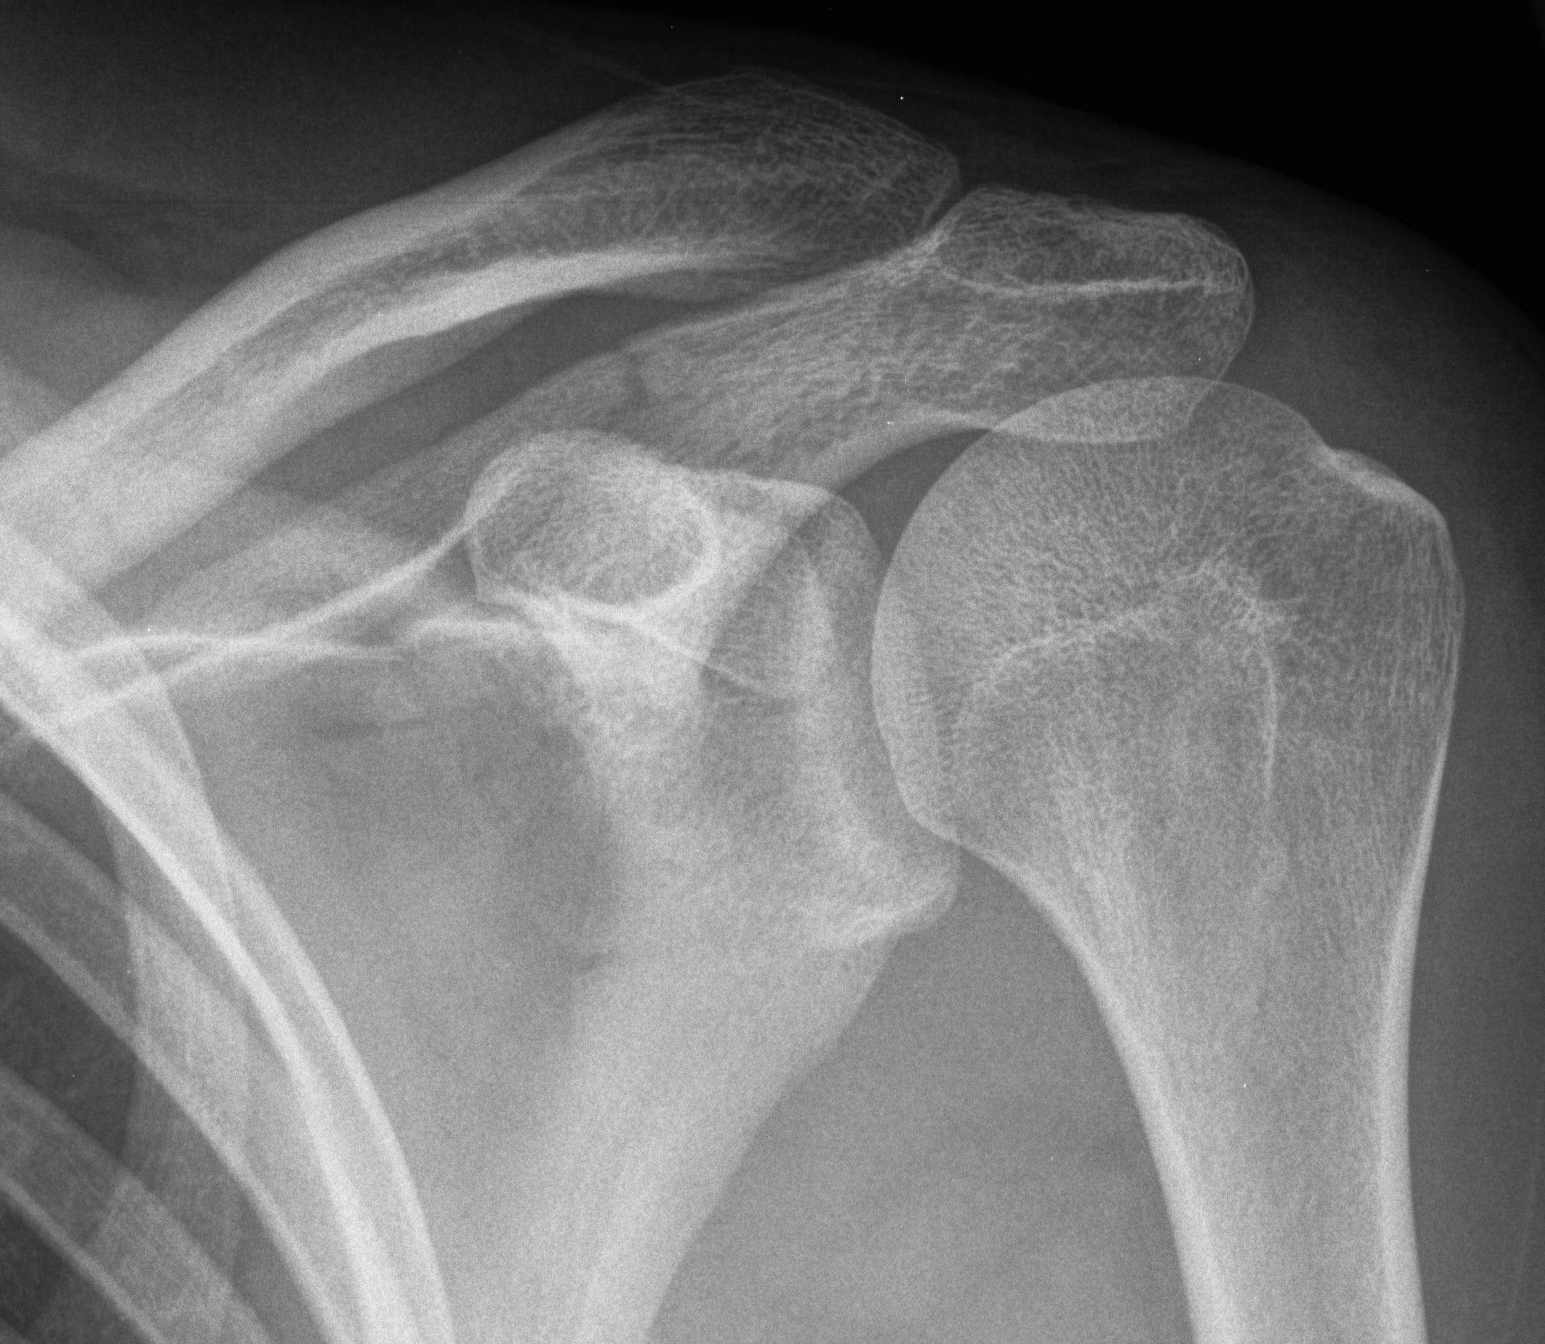

Scapula Fracture X Ray Scapula Bone Break learn about the causes, symptoms, diagnosis, and treatment of scapula fractures, a rare but serious injury that often requires surgery. a shoulder fracture is a broken bone in your shoulder joint, usually caused by a traumatic injury. Learn about the symptoms, causes and treatments of this condition, including when surgery may be needed. You may need a sling,. Scapula Bone Break.

Trauma Xray Upper limb gallery 1 Scapula fractures Scapula Bone Break a shoulder fracture is a broken bone in your shoulder joint, usually caused by a traumatic injury. a scapula fracture is a break in the shoulder blade bone caused by direct trauma. Learn about the symptoms, causes and treatments of this condition, including when surgery may be needed. You may need a sling, surgery or. the shoulder. Scapula Bone Break.